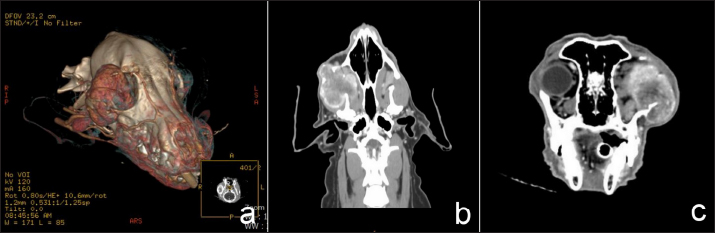

A female Cocker Spaniel dog aged 11 years was presented with a history of globe displacement of the right eye for 3 months. Ophthalmic examination revealed exophthalmos and third eyelid protrusion OD. Menace response, dazzle reflex, and pupillary light reflex were positive OU (oculus uterque; both eyes). Intraocular pressure (IOP) measured using a rebound tonometer (Icare®TonoVet; Icare Finland Oy; Helsinki, Finland) was slightly increased OD (IOP=29 mmHg) and within the normal limit OS (IOP=12 mmHg). Fundic examination was normal OU. Topical 1% brinzolamide (Azopt®; Alcon-Couvreur SA; Belgium) every 8 hours a day OD and artificial tears ointment with lanolin (Duratear: Alcon-Couvreur SA; Belgium) every 12 hours a day OU were prescribed. Computed tomography (CT; Optima CT600; GE Healthcare; USA) was planned to estimate the invasiveness of the lesion. CT demonstrated a mass effect with contrast enhancement in the right retrobulbar, maxilla, zygomatic, and temporal areas invading the right mandibular area with a periosteal reaction. Right zygomatic and temporal bone lysis was evident (Fig. 1). There was no detectable nodule metastasis in lung fields. The diagnosis was retrobulbar tumor OD. Cytologic examination at the retrobulbar area was sarcoma. Physical examination, hematology, and blood chemistry results were within normal limits. The planned treatment was tumor biopsy and surgical mass excision by exenteration combined with partial orbitectomy and zygomatic arch removal.

Fig. 1. Three-D (a), transverse (b), and dorsal (c) computed tomographic images in right retrobulbar, zygomatic, and temporal areas revealed a soft tissue mass involving periosteal bone with lysis of zygomatic and temporal bones.